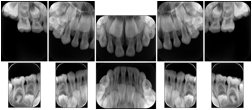

Intra-oral radiography typically involves acquisition of multiple images of various parts of the dentition. Many digital radiographic systems offer customized templates that are used for displaying the images in a study on the screen. These templates may also be referred to as mounts or view sets. The Structured Display Object represents a standard method of encoding and exchanging the layout and intended display of Structured Displays. A structured display object created in this manner could be stored with a study and exchanged with images to allow for complete reproduction of the original exam.

3. A dental provider wishes to capture a series of DICOM IO images for the patient’s dentition. The tooth morphology, teeth are divided into molars, premolars, canines and incisors, and a number of images for each jaw. The anatomic information was captured utilizing the triplet of schema. This standard code sequence is based on ISO 3950-2010, Dentistry - Designation system for teeth and areas of the oral cavity.

Every IO image should have anatomic information either through the primary or modifier sequence.

In most standard cases, images are oriented in structured layouts. These structured displays are useful to be shared between providers for reference purposes.

Table OO.1.1-1 shows structured display standard templates, where Viewset ID is based on the Japanese Society for Oral and Maxillofacial Radiology (JSOMR) classification provided by JIRA (Japan Medical Imaging and Radiological Systems Industries Association, www.jira-net.or.jp). Expected or typical teeth to be imaged location, region and designation codes are based on ISO 3950-2010, Dentistry - Designation system for teeth and areas of the oral cavity. For all the hanging protocols listed in OO.1.1-1, the value to use for Hanging Protocol Creator (0072,0008) is "JSOMR" and the value to use for Hanging Protocol Name (0072,0002) does not include "JSOMR" (e.g., "DL-S001A", not "JSOMR DL-S001A").